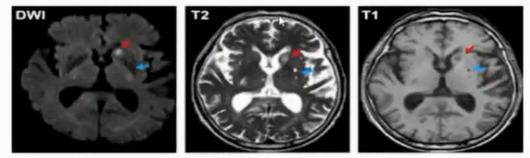

常规影像技术与SVD诊断见下图。

(1)陈旧性脑梗死

FLAIR影像结果显示,中间是低信号,周围是高信号。据此进行鉴别诊断。

(2)急性腔梗、扩大的脑血管周围间隙鉴别

红色箭头:急性腔梗, DWI:高信号;T 2高信号;T 1:低信号;

蓝色箭头:扩大的血管周围间隙, DWI:低信号;T 2高信号, 接近脑脊液的信号;T1:低信号,周围没有增生的胶质细胞。

(3)陈旧性脑出血鉴别诊断

T2WI高信号伴周围低信号环(含铁血黄素沉积)。

(影像由南京鼓楼医院提供)